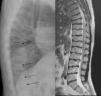

La ML III se manifiesta aproximadamente entre los 3 y 5 años de edad, con anomalías esqueléticas, alteraciones faciales, talla baja, inteligencia normal o retraso mental leve, opacidad corneal y escoliosis, a diferencia de otras formas de ML que sí tienen afectación visceral y un pronóstico vital sombrío en la infancia2,3. En la ML III la evolución es lenta, pudiendo alcanzar hasta la quinta década de la vida4. Las alteraciones óseas en la infancia pueden confundirse con artritis idiopática juvenil o esclerodermia, fundamentalmente por la afectación de las manos5,6. Los hallazgos radiológicos característicos de las manos son huesos del carpo pequeños e irregulares y falanges proximales relativamente anchas5 (fig. 1). En la columna lumbar, displasia vertebral con delineación irregular de los cuerpos vertebrales3, imágenes que se confirman en la RM (fig. 2). En la pelvis, displasia progresiva de las caderas, con acetábulos aplanados y destrucción de las cabezas femorales con coxartrosis secundaria2 (fig. 3).